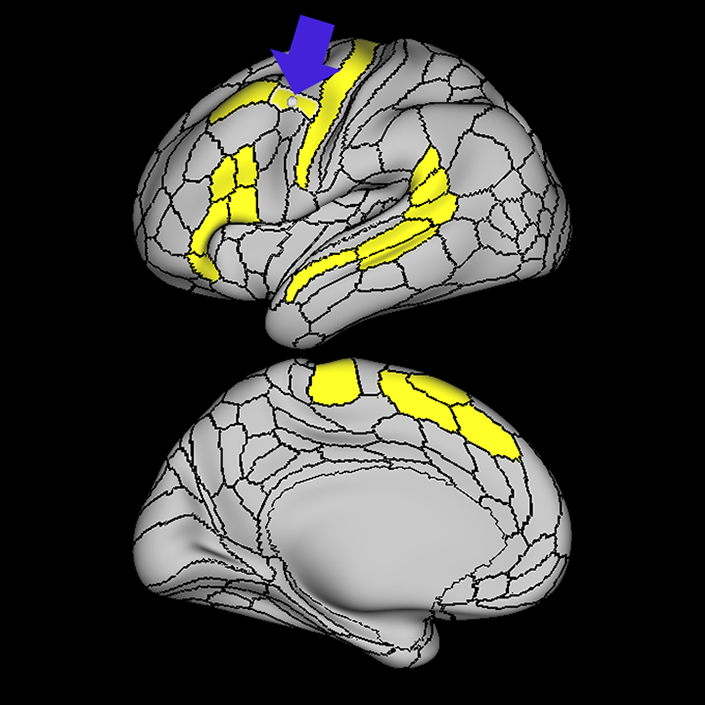

ᐅ SummaryArea 44: part of the inferior frontal gyrus of the lateral frontal lobe. Translates abstract and intentional information in the prefrontal cortex to more detailed representations to help guide the production of verbal and manual actions. In addition to its known association with Broca's area, is sometimes represented as part of Broca's complex ᐅ Where is it?Area 44 is at the posterior most part of the inferior frontal gyrus. It is the anterior bank of pars opercularis of the IFG. ᐅ What are its borders?Area 44 borders area 45 anteriorly and area 6r posteriorly. Area 8C is its medial border and its inferior border is wedged between then upper borders of Areas 6R and 6V. Its superior edge borders IFSp and IFJa. Its opercular surface is FOP4. ᐅ What are its functional connections?Area 44 demonstrates functional connectivity to areas SFL, IFSp, IFJa, 45, 47s, 47L, 9a, 9m, 8AV, 8BL and 8C in the dorsolateral frontal lobe, area 8BM in the medial frontal lobe, area 55b in the premotor areas, areas FOP5, AVI and PSL in the insula- opercular region, areas TGd, STSdp and STSvp in the temporal lobe, areas PFm, and PGi in the inferior parietal lobe, and no areas in the medial parietal lobe. ᐅ What are its white matter connections?Area 44 is structurally connected to the arcuate/SLF and the FAT. Connections with the arcuate/SLF project posteriorly and wrap around the Sylvian fissure to the middle temporal gyrus to end at TE1a and TE1m. There are also projections from the arcuate/SLF before it terminates to parcellations A5 and STSdp. The majority of the inferior connections of the frontal aslant tract end at 44, the tract is connected superiorly to superior frontal gyrus parcellations SFL, 6ma and s6-8. Local short association bundles are connected with 45 and 8C. White matter tracts from 44 in the right hemisphere have less consistent connections with the arcuate/SLF. ᐅ What is known about its function?Area 44 translates abstract and intentional information in the prefrontal cortex to more detailed representations to help guide the production of verbal and manual actions. Area 44, in addition to its known association with Broca's area, is sometimes represented as part of "Broca's complex", including Brodmann Areas 45, 46, 47 and the mesial supplementary motor area of 6, which contribute to a frontal-subcortical circuit. The right pars opercularis has also been implicated in cognitive inhibition in the overall context of working memory. |

A: lateral-medial

B: anterior-posterior

C: superior-inferior

DTI image |